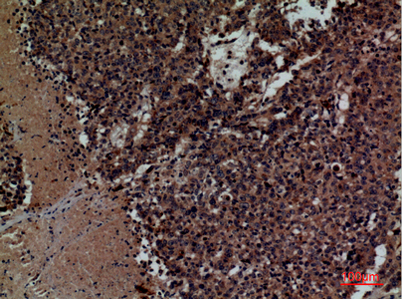

Product name: CD158z rabbit pAb

Dilutions: Western Blot: 1/500 - 1/2000. IHC-p: 1:100-300 ELISA: 1/20000. Not yet tested in other applications.

Immunogen: The antiserum was produced against synthesized peptide derived from the Internal region of human KIR3DL3. AA range:231-280